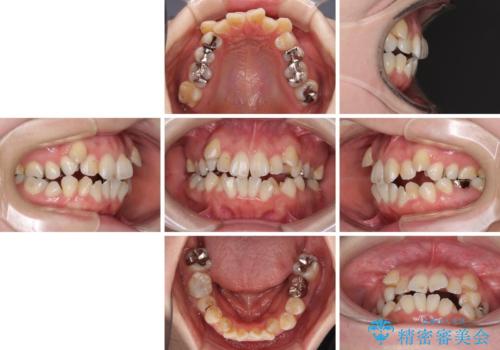

- 八重歯やデコボコを気にして来院された患者様です。

お住まいから船での通院となることから、補助装置を使用しながらインビザラインにて上下左右第一小臼歯4本を抜歯した矯正治療を行うこととしました。

ところが、インビザラインでの自己管理が煩わしいと感じてしまい、途中で矯正治療を投げ出すことになってしまいました。

相談の上、表側の目立ちにくいワイヤー装置により矯正治療を継続していくこととしました。